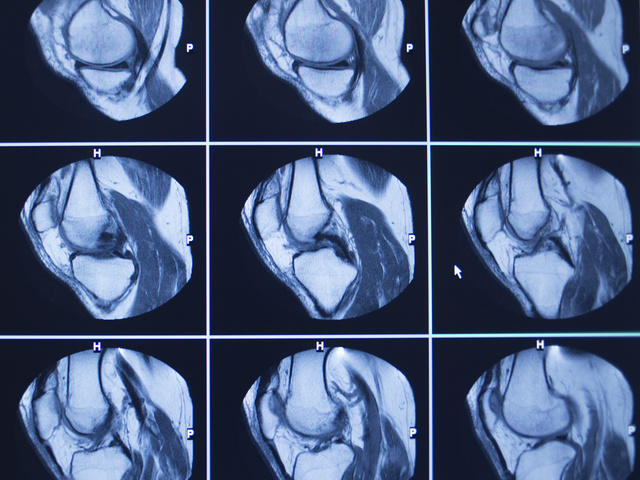

半月板

半月は円周状(フープ)で、クッションと安定性を確保する役割をはたしています。

傷ができる(損傷)ことによる問題は、ひっかかりを感じたり、水(関節液)がたまったり、急に膝が動かなくなる“ロッキング”という状態がおこることです。膝が抜ける(くずれる)こともあります。

半月板は膝の屈伸や捻りの動きのたびに、移動(スライド)や変形をする部分で、特に外側半月は大きく動きます。

ですので、断片(フラグメント)があると、動くときに傷口(ギャップ)が広がり問題を起こしやすくなります。